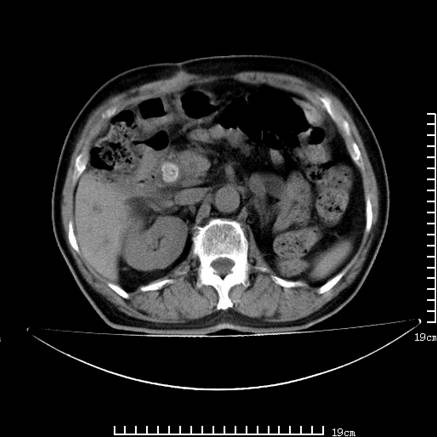

以下是引用zsl6918在2008-7-19 21:53:00的发言:[br]胆总管结石并胆系感染,胆囊切除术后改变。

以下是引用sch2008在2008-7-19 22:03:00的发言:[br]肝内胆管及胆总管积气,并胆总管结石,考虑;胆囊切除术后,胆系感染

以下是引用xinliheng001在2008-7-19 21:59:00的发言:[br]胰头段胆管结石肝内外胆管扩张积气。

以下是引用liaoqiang在2008-7-19 22:26:00的发言:[br]胆总管结石伴胆系感染。